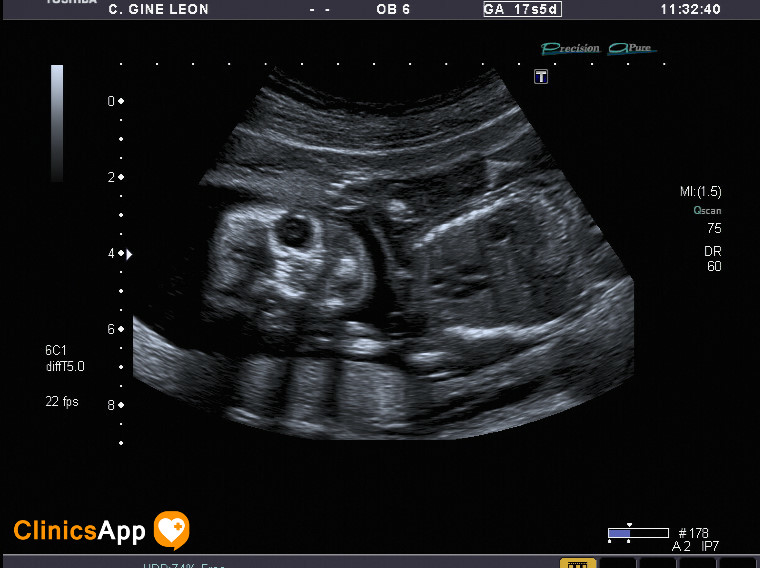

Tercera ecografía (parece que es un niño) Aquí tenemos las fotos de la ecografía de hoy. Parece ser que es un niño, ya no quedan muchas dudas. Fecha publicación 04/05/2016 Publicada por papá Publicada en Fotos, Galerías, Prenatal, Vídeos Comentarios 0 Entrada anterior: Segunda ecografía (mismo día por la tarde), ¡y con vídeo! Entrada siguiente: Cuarta ecografía ¡en 3D! Deja una respuesta Cancelar la respuestaComentario * Nombre * Correo electrónico * Web Guarda mi nombre, correo electrónico y web en este navegador para la próxima vez que comente. Recibir un correo electrónico con los siguientes comentarios a esta entrada. Δ